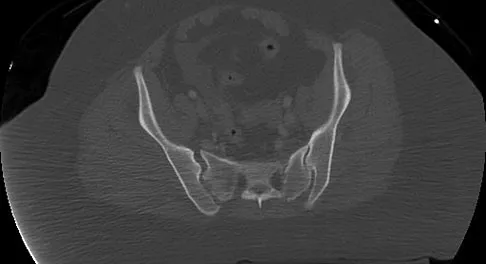

Which of the following types of displaced posterior pelvic disruptions must undergo anatomic reduction and internal fixation to ensure the best clinical outcome?